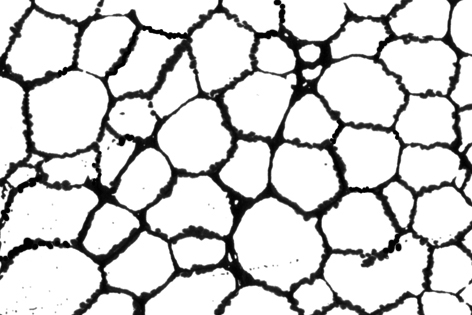

細胞存在パターン;左:hypo-diffuse 右:hypo-patchy

Hypo-diffuseは存在すれば「病気」の異常な状態とみなしてよい。Hypo-patchyは高齢者骨髄に似る所見